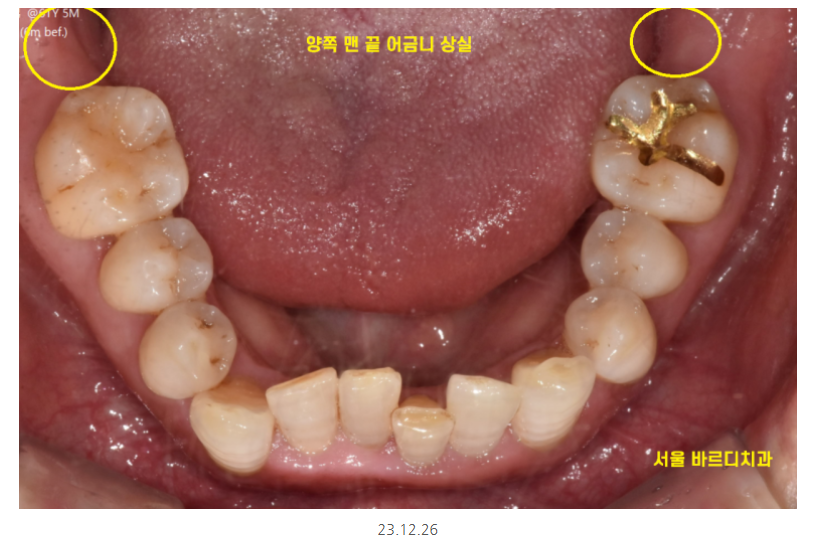

하남시청치과 처음 방문해주셨을 때

왼쪽, 오른쪽 맨 아래 끝에 어금니가 상실한 채로 오셨습니다.